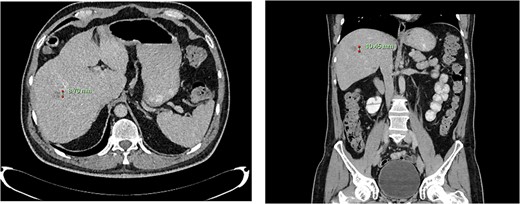

Computed tomography dated 12 March 2013 of the abdomen and pelvis measuring 8.70 mm (anterior–posterior) lesion at liver segment 5/6 in axial (left) and coronal (right) view.